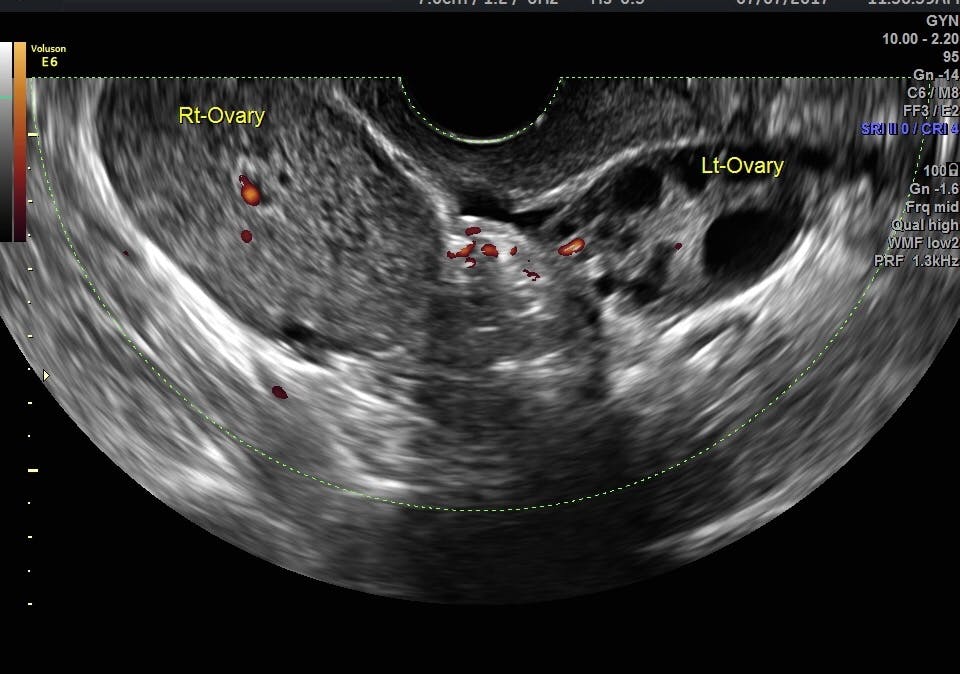

Female Pelvic Ultrasound Report / 32 Year Old Woman With Pelvic Pain And Irregular Menstrual Periods Mdedge Obgyn : Sonographic findings in adnexal torsion:

Polycystic ovarian syndrome ovarian mass. Watch this and know what to expect before your appointment. A pelvic ultrasound is a noninvasive diagnostic exam that produces images that are used to assess organs and structures within the female pelvis. Aid radiologists in accurate diagnosis and management of. Primary indications for female pelvic us examination are pelvic pain, abnormal vaginal bleeding, and suspicion of histologic changes reported with tamoxifen therapy include endometrial hyperplasia leiomyomas are the most common tumor of the female pelvis, occurring in up to 40% of women. Pelvic pain is a common indication for ultrasound examinations in female pediatric patients. What is free pelvic fluid? A pelvic ultrasoundallows quick visualization of the female pelvic organs and structures including the uterus, cervix, vagina, fallopian tubes and ovaries. Keywords female ultrasound endometrial stripe . Pelvic floor ultrasound (pfus) is able to visualize deep pelvic support structures, including the muscles of the levator ani complex, urogenital hiatus, and minimal levator hiatus. Ultrasound is a safe and widely used imaging technique. A pelvic ultrasound typically is covered by health insurance when ordered by a doctor for diagnosis of a problem. In female pelvic ultrasound imaging, and we hope it will.

2000 dane b, dane c, kiray m, cetin a. Pelvic ultrasound in the postabortion and postpartum patient. A transabdominal (ta) evaluation and a transvaginal (tv) / endova. Ultrasound of the female pelvis— presentation transcript clinically, patients present with a sudden onset of pelvic pain. The female pelvis is an anatomic region which is quite complex, because it contains some organs and the are several gynaecological causes responsible for pelvic tumours.